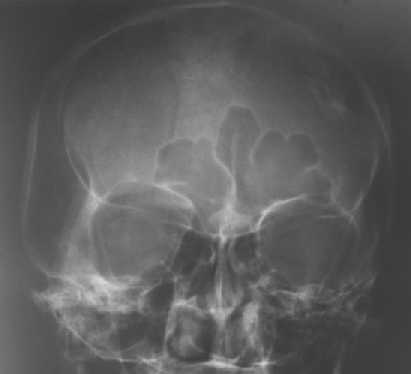

Deppressed fractures :